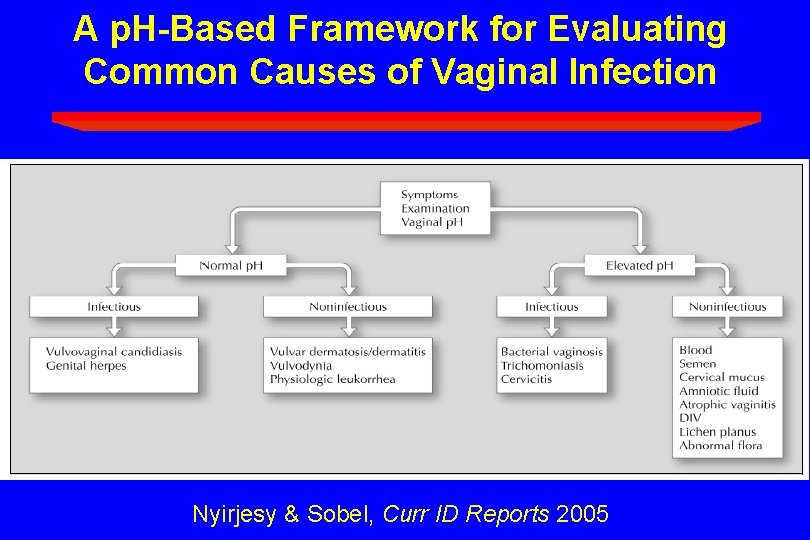

A p. H-Based Framework for Evaluating Common Causes of Vaginal Infection Nyirjesy & Sobel, Curr ID Reports 2005